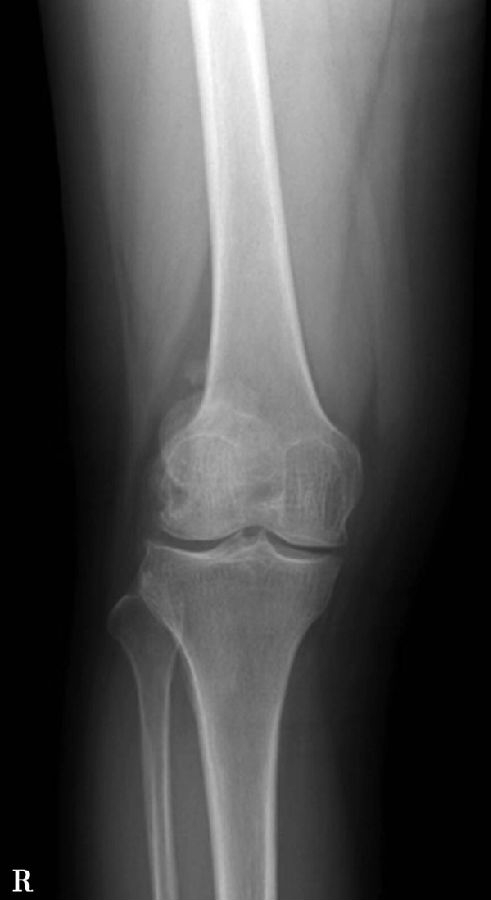

正常髌骨中心点应位于下肢轴线上或稍内侧(图1)。对于髌骨不稳定,膝关节正位像可见髌骨偏离正常的位置,向外侧移位(图2、图3)。

图1 正常膝关节正位X线平片显示了髌骨的正常位置